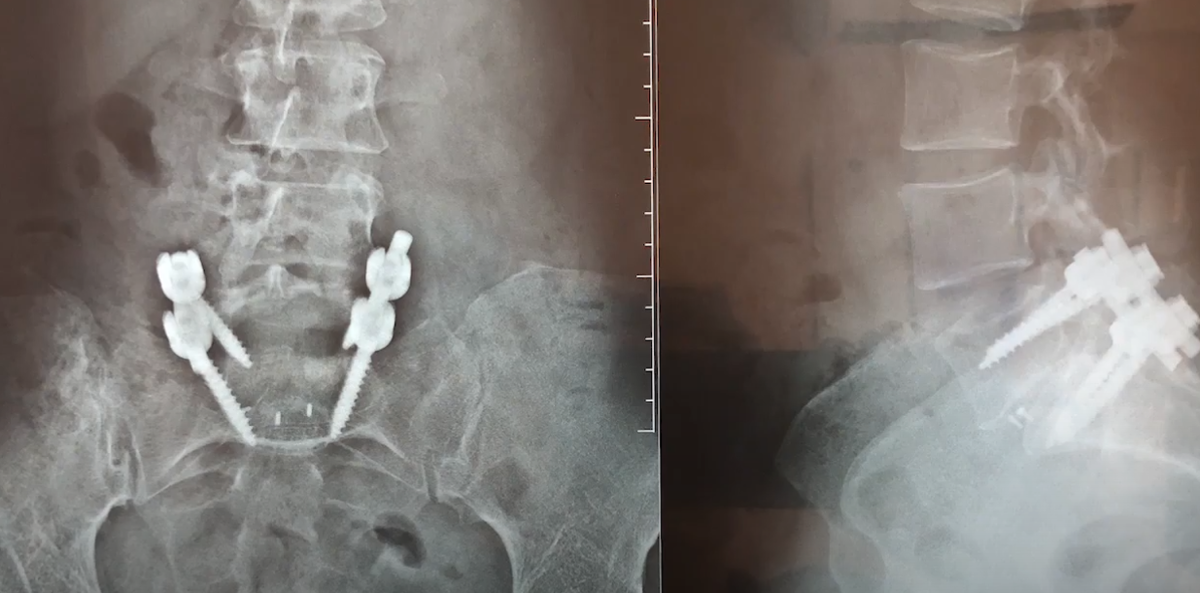

Пациенту со спондилолизным спондилолистезом выполнялась операция по Хармсу, устанавливались кейдж и 4 винта, производилась адекватная декомпрессия.

Стабилизация по Хармсу